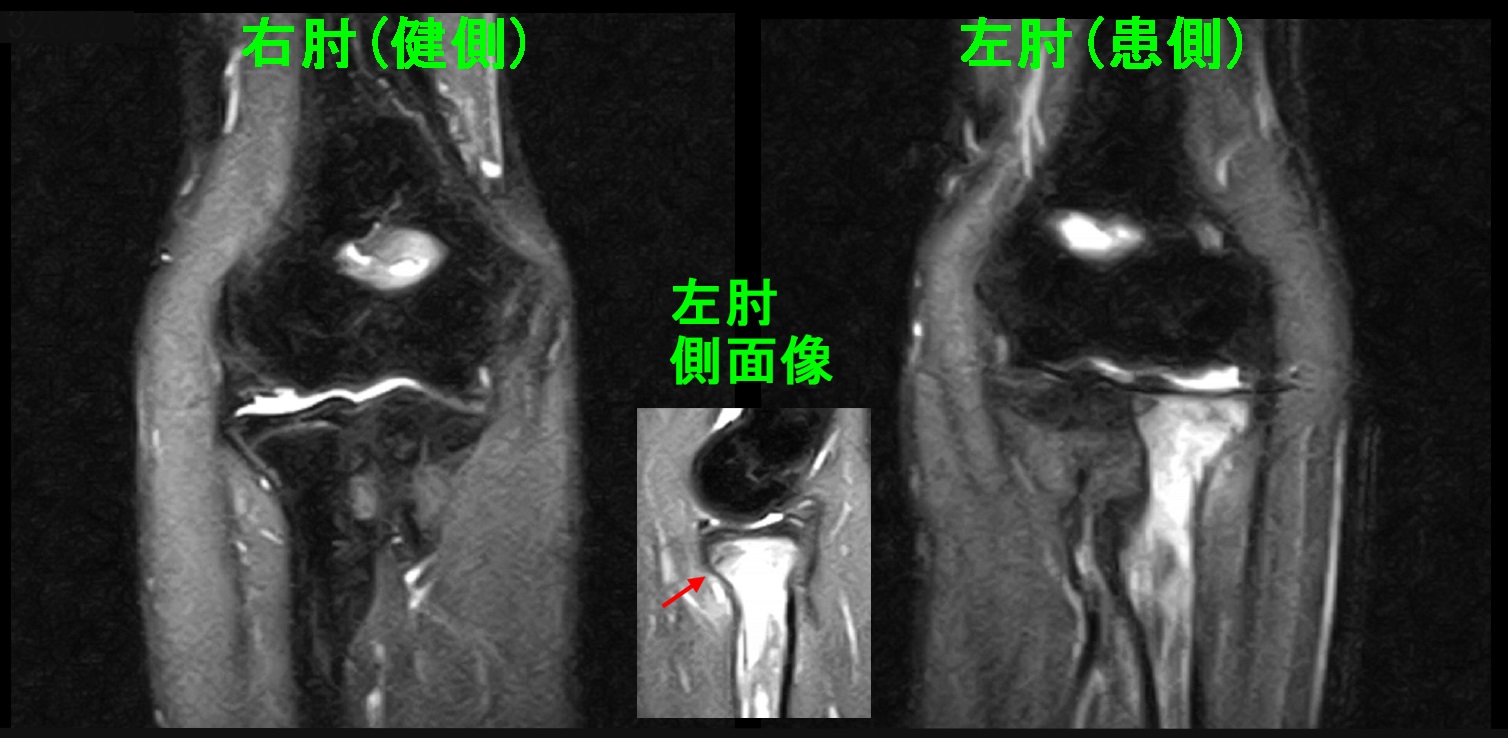

15才男 初診MR.jpg

MRI検査でのSTIR条件の画像ですが、左肘の橈骨は本来骨は黒く描出されるのですが、白くなっています。白いのは骨の中に出血した状態を示しています。側面像では赤矢印の部分が骨折部分となります。